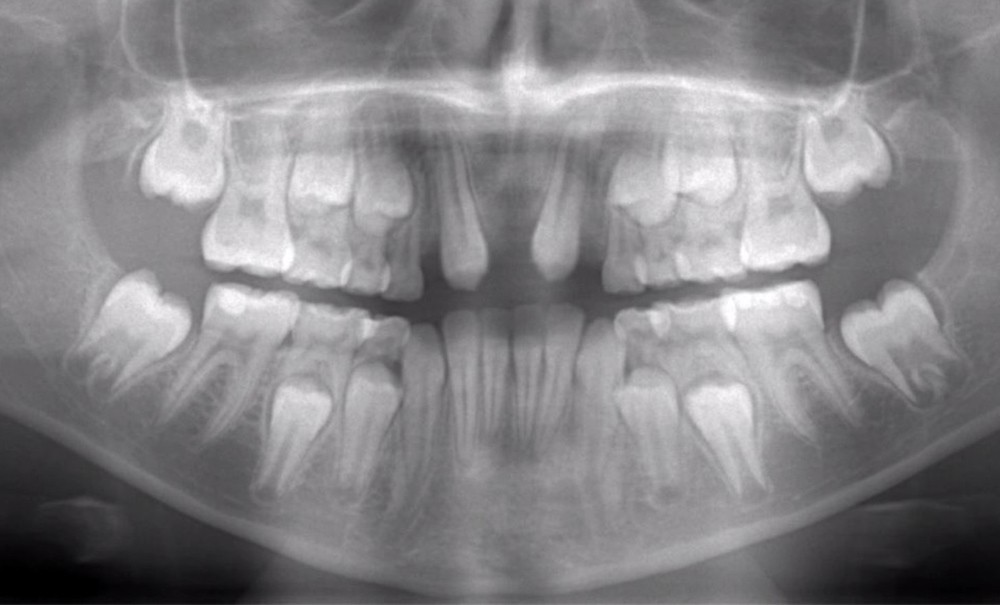

L’âge de survenue de ces traumatismes se situe entre 8 et 12 ans. À cet âge, les incisives permanentes ont généralement fait leur éruption et leur ligament parodontal possède une résistance moindre aux forces extérieures. La partie antérieure des maxillaires est la région la plus sujette aux traumatismes pendant l’enfance et, à la suite de ces derniers, une perte de dents peut se produire. Remplacer les dents manquantes a toujours été l’un des défis des chirurgiens-dentistes chez les enfants et les adolescents, car leur croissance dentofaciale n’est pas complète. Dans une telle situation, la conservation de l’espace de la dent manquante est nécessaire jusqu’à la fin de la période de croissance dento-faciale de l’individu [2].

Dans les situations où elle est réalisable, l’autotransplantation de prémolaires peut être une alternative thérapeutique. Cette technique consiste à transplanter une dent d’un site donneur à un site receveur chez le même individu [3].

L’autotransplantation peut être définie comme le transfert atraumatique d’une dent de son alvéole vers un autre site chez le même individu.

Le site récepteur peut être un site d’extraction ou une alvéole nouvellement préparée chirurgicalement. L’autotransplantation est :